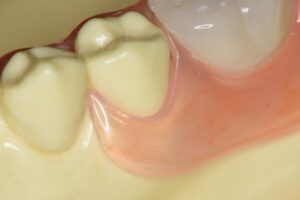

テレスコープ義歯とは──残った歯を守る発想

ここからはテレスコープ義歯の話です。テレスコープ義歯は、クラスプ義歯とは全く逆の発想で作られます。まず歯を加工して金属の「茶筒状のキャップ(内冠)」で包み、その上に外冠と呼ばれる義歯本体を精密に重ね合わせます。装着後は、歯と義歯が一体化するように設計されているのです。

この構造により、噛む力は歯が最も強いとされる上下の歯軸方向にだけ伝わります。硬い食べ物でも力が分散され、歯や歯ぐきに無理なく伝わるため、歯への局所的な負担が小さくなります。着脱も歯軸方向に沿った動きなので、横揺れを生じにくく、歯にかかる力が安定するのです。これが「リジッドサポート(剛性支持)」という考え方です。

さらに、義歯と歯が一体化していることで「噛んだ」という感覚が歯周感覚として脳に伝わりやすくなります。その結果、顎の動きを脳が察知しやすく、歯があったときに近い繊細で自然な咀嚼が可能になります。